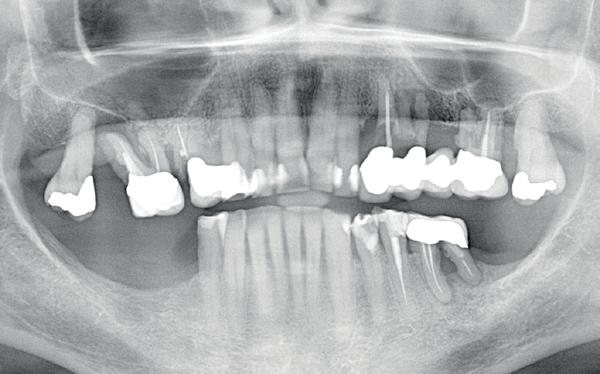

Casus

In deze casus is extractie van de 37 geïndiceerd in verband met een fistel en restpockets, zoals zichtbaar op de röntgenfoto’s (afbeelding 1). Duidelijk te zien is de forse peri-apicale ontsteking en het botverlies bij de 37, dat zowel richting buccaal als linguaal doorloopt. De 37 wordt atraumatisch verwijderd. Er is aan de linguale zijde veel bot verloren en er is sprake van een perforatie aan de buccale zijde.

Er wordt besloten om botmateriaal te plaatsen in de extractie-alveole. Vervolgens wordt het afgesloten met een titanium versterkt d-PTFE membraan (afbeelding 2). Na vier weken wordt het membraan verwijderd.

Zes maanden na extractie wordt het implantaat 37 geplaatst. Er is sprake van een goede genezing en de processushoogte en -breedte zijn behouden en opgebouwd. Ook is er zichtbaar gekeratiniseerd weefsel

1 2 Ridge preservation met d-PTFE membranen 35

gewonnen. De wond kan na het plaatsen van een healing abutment primair gesloten worden (Afbeelding 3a-3d).

In afbeeldingen 4a-c is het resultaat drie maanden na het plaatsen van het implantaat te zien. De genezing is volledig en de verwijzer kan de suprastructuur vervaardigen (afbeelding 4a-4c).

In afbeeldingen 5a-d is de implantaatkroon 37 te zien, twee jaar na plaatsing. Op de röntgenfoto is herstel van zowel corticaal als spongieus bot te zien. (De CB-CT was vervaardigd in verband met implantologische indicatie in het naastliggende gebied).

Deze casus illustreert dat er op een voorspelbare manier een ridge preservation procedure uitgevoerd kan worden met een d-PTFE membraan en er daarna voorspelbaar geïmplanteerd kan worden.